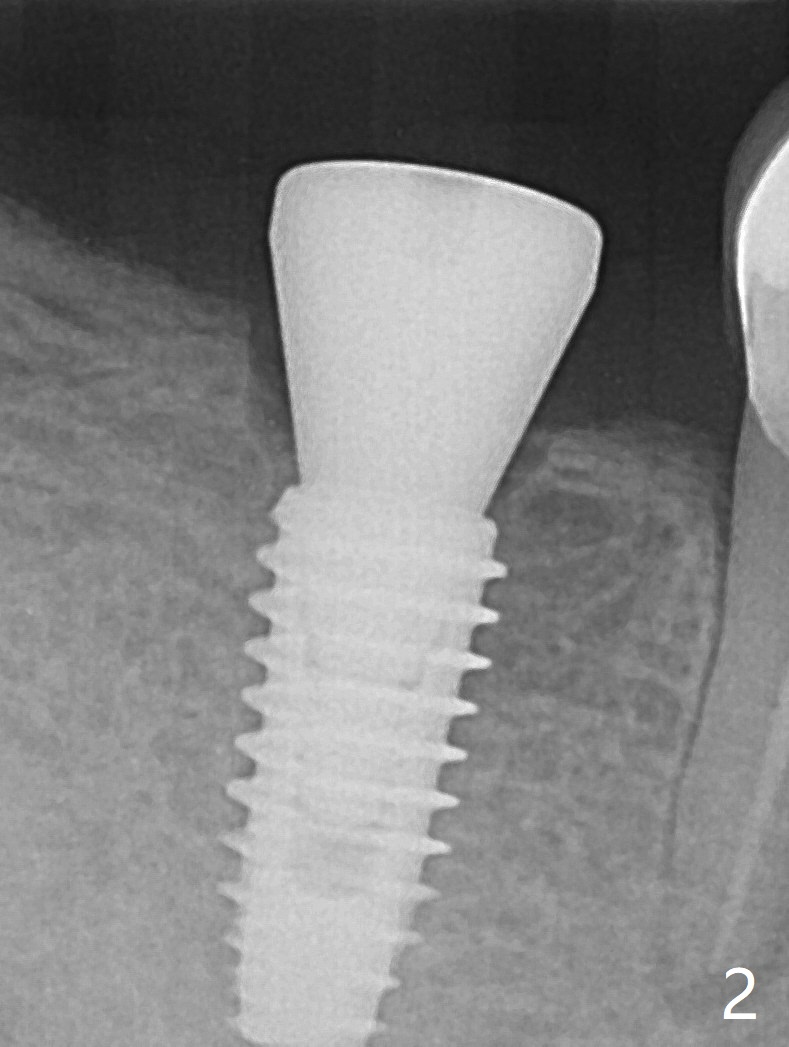

The female patient has limited mouth opening, complicated further by supraerupted opposing tooth. It is difficult to insert point drill and tap drill for #30 implant placement with guide. The former has to be inserted into the sleeve of the guide extraorally; two of them are placed intraorally together, while the tap drill is not used at all. When a 4.5x10 mm implant is placed, it is difficult to use #2 sensor to take PA. Finally a BW is taken with #2 sensor (Fig.1), while a PA is taken with #1 sensor (Fig.2). CT is taken to show clearance of the implant from the Inferior Alveolar Canal (Fig.3,4). To seat healing and later cemented abutments completely, a 5.5 mm profile drill is applied after implant placement; the outline is illustrated by red dashed line in Fig.1''. The elongated mesiolignual cusp of the tooth #3 has to be trimmed after placement of a 6x5 mm healing abutment. In fact trimming prior to osteotomy could solve the mouth opening partially. After removal of the 6x5 mm healing abutment, a 4.5x4(3) mm cemented abutment is incompletely seated (Fig.5 <) apparently due to proximity to the mesial crest (*). With reuse of a 4.6 mm profile drill, the abutment is fully seated (Fig.6), confirmed clinically by more clearance from the opposing tooth (Fig.7). Complete occlusal clearance is obtained by reduction of the opposing cusps without sensitivity since the tooth is nonvital (*). Return to No Deviation Xin Wei, DDS, PhD, MS 1st edition 05/28/2020, last revision 09/04/2020